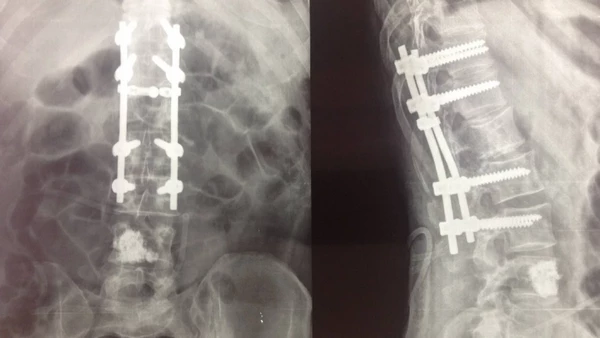

Ідентифікація раніше встановленого спинномозкового обладнання може бути складною і забирати багато часу, коли пацієнту потрібна ревізійна операція. Детальна інформація про модель і тип імплантату часто відсутня, коли пацієнтів направляють в інше місце, або може бути відсутнім в примітках до операції.

Для побудови свого класифікатора дослідники використовували 1072 рентгенограми, що показують післяопераційні види встановлених грудопоперекових імплантів, виготовлених п’ятьма різними компаніями-виробниками.

Модель комп’ютерного зору перевершила двох хірургів та трьох представників виробника як за точністю (79% проти 44%), так і за часом завершення (14 секунд проти 20 хвилин).